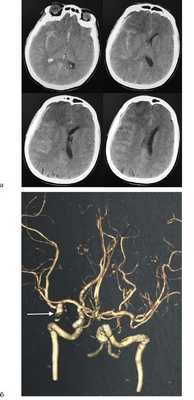

Данные коагулограммы в норме. Проведена экстренная КТ головного мозга. Внутривенно болюсно введен маннитол из расчета 1 г на 1 кг массы тела. При компьютерной томографии головного мозга выявлено базальное САК с преобладанием в области правой сильвиевой щели, также острая субдуральная гематома в правой лобно-височно-теменной области объемом около 60 см 3 . Дислокация срединных структур влево на 8 мм. Ипсилатеральный желудочек компримирован. Сдавлена обводная цистерна справа. В режиме ангиографии выявлена артериальная мешотчатая аневризма бифуркации М1 сегмента средней мозговой артерии (СМА) справа (рис. 1).

Рис. 1. КТ головного мозга: массивное базальное САК. а — острая субдуральная гематома справа. Спиральная КТ-ангиография: артериальная аневризма бифуркации СМА справа (указано стрелкой) (б).